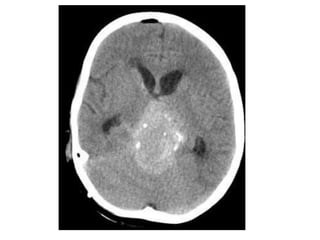

Axial nonenhanced CT shows a large pineal region mass with resultant hydrocephalus ,

the pineal calcifications are exploded toward the periphery (arrows)

b) Pineoblastoma : -Highlymalignant PNET (Primitive Neuroectodermal Tumors) -In patients with trilateral retinoblastoma, Pineoblastoma may develop in patients with familial and or bilateral retinoblastoma -(Exploded calcifications) along outside of mass (peripherally), unlike germinoma which engulfs and induces calcification of the pineal gland -Dense enhancement -Larger, more heterogeneous with much greater propensity for local invasion and CNS dissemination

Axial nonenhanced CTshows a large pineal region mass with resultant hydrocephalus , the pineal calcifications are exploded toward the periphery (arrows)